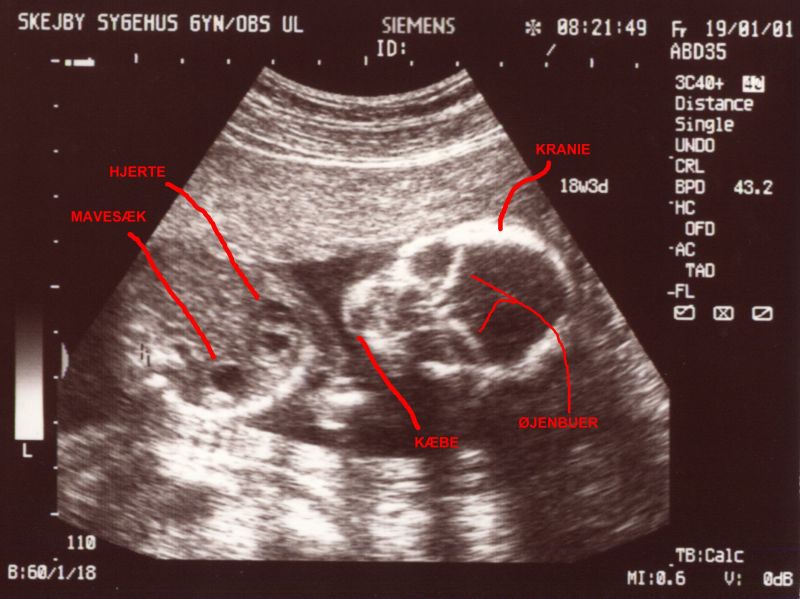

Scannings at the 12th and 19th week of the pregnancy.

Full picture from scanning in the 12th week. Lots of life and movement in there. Same picture, but with explanations. It takes a bit of practice to see anything on these images. Facial shot - looks eerie, but she was looking all the time curiously at the scanner. Really detailed - even though she's 12 cm from head to butt here. Same picture, but with explanations. Sorry, it's all in danish.